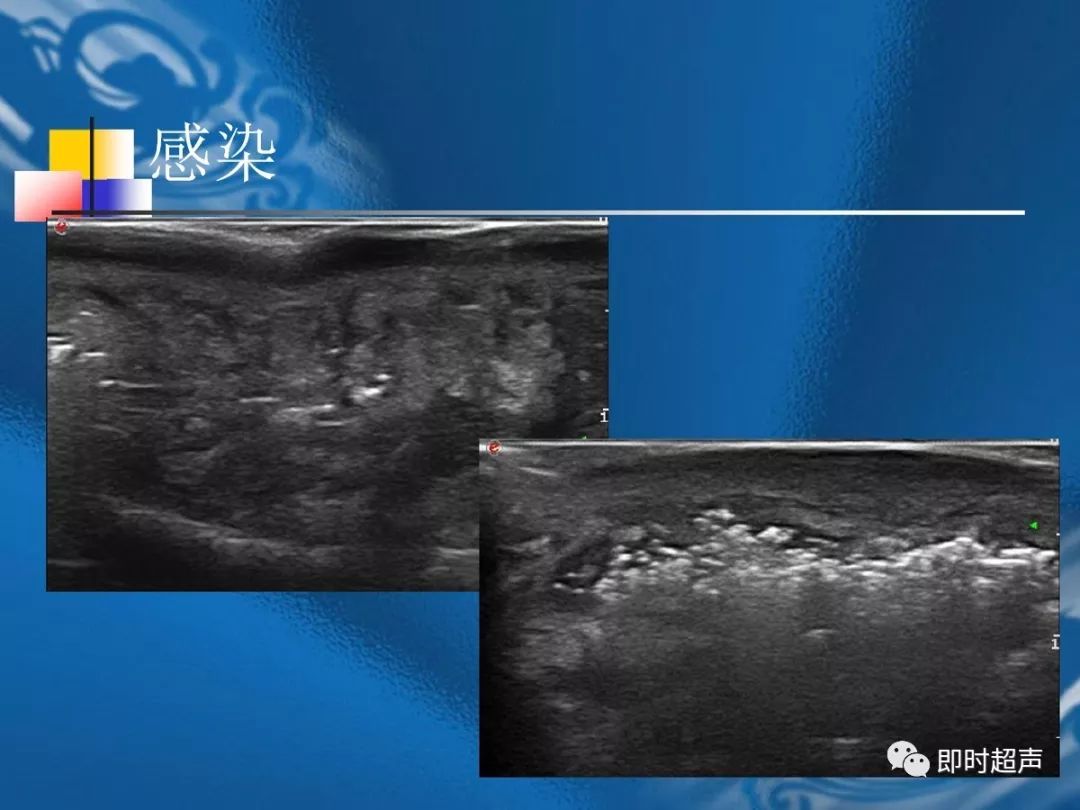

桡骨茎突狭窄性腱鞘炎